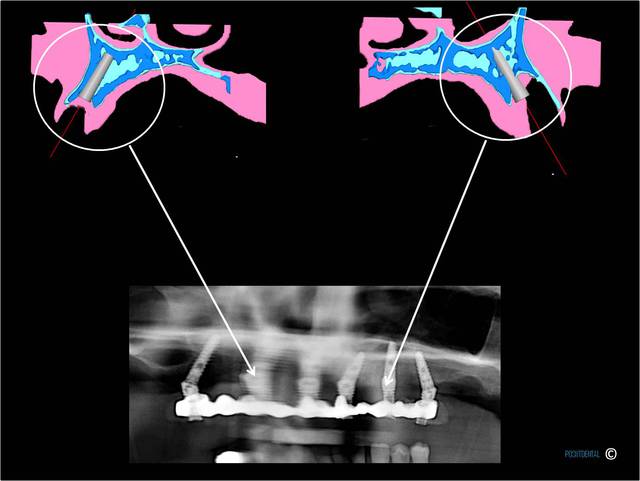

2h30 dtnqhc - Eugenol

au maxillaire

A la mandibule :

Au maxillaire , même moi qui ne suis qu'un petit , petit omnipraticien , et surtout pour le dernier à droite d'implant c'est hallucinant et avec mon expérience en bricolage , bin ce all on5 et demi me fait peur . Je ne vois pas pourquoi virer un bloc antérieur et ne pas profiter des alvéoles de chaque dent , en postérieur attendons que Pp très au fait revienne .